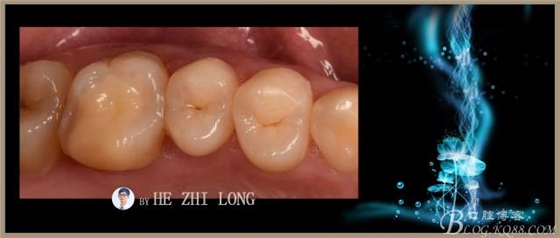

術(shù)后即刻調(diào)合拋光照片:(由于鑄瓷嵌體很難達(dá)到烤瓷嵌體的色澤,因此從牙本質(zhì)到牙釉質(zhì)的色澤沒(méi)有很好的過(guò)度,稍有點(diǎn)遺憾。)

術(shù)前術(shù)后對(duì)比照片:

術(shù)后半個(gè)月照片: